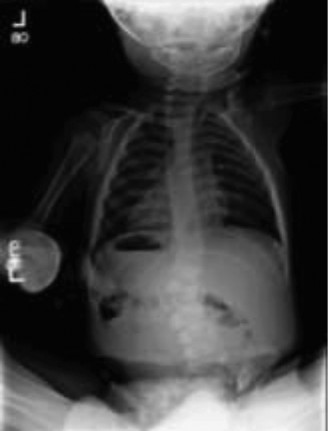

Plain Radiography Evaluation

The initial diagnostic modality consisted of standing full-length posteroanterior and lateral radiographs of the entire spine. The PA radiograph revealed a severe, short-segment, rigid dextroscoliosis centered at T8. The Cobb angle measured 52 degrees. The films clearly delineated a fully segmented T8 hemivertebra on the right (convexity) and an unsegmented osseous bar spanning from T7 to T9 on the left (concavity).

The lateral radiograph demonstrated a localized lordosis at the apex, confirming the three-dimensional complexity of the deformity. Supine bending films were obtained, which confirmed the absolute rigidity of the curve; the Cobb angle remained unchanged at 52 degrees on maximal side-bending. This rigidity is the pathognomonic radiographic signature of the unilateral unsegmented bar.